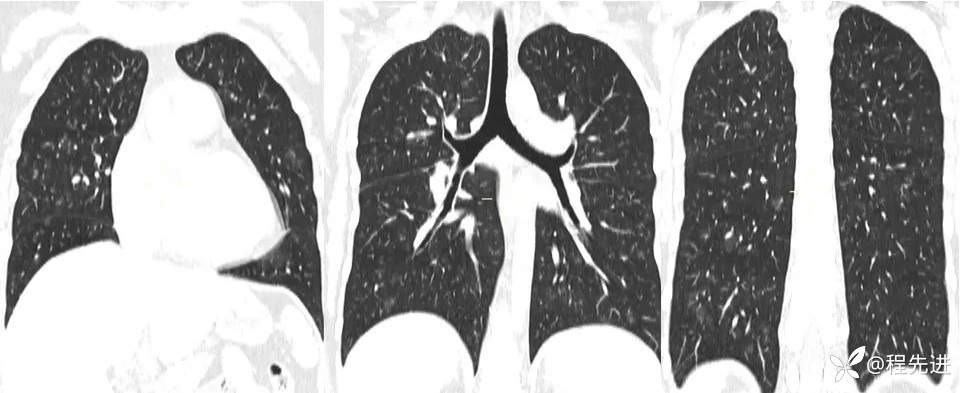

一月余前CT: